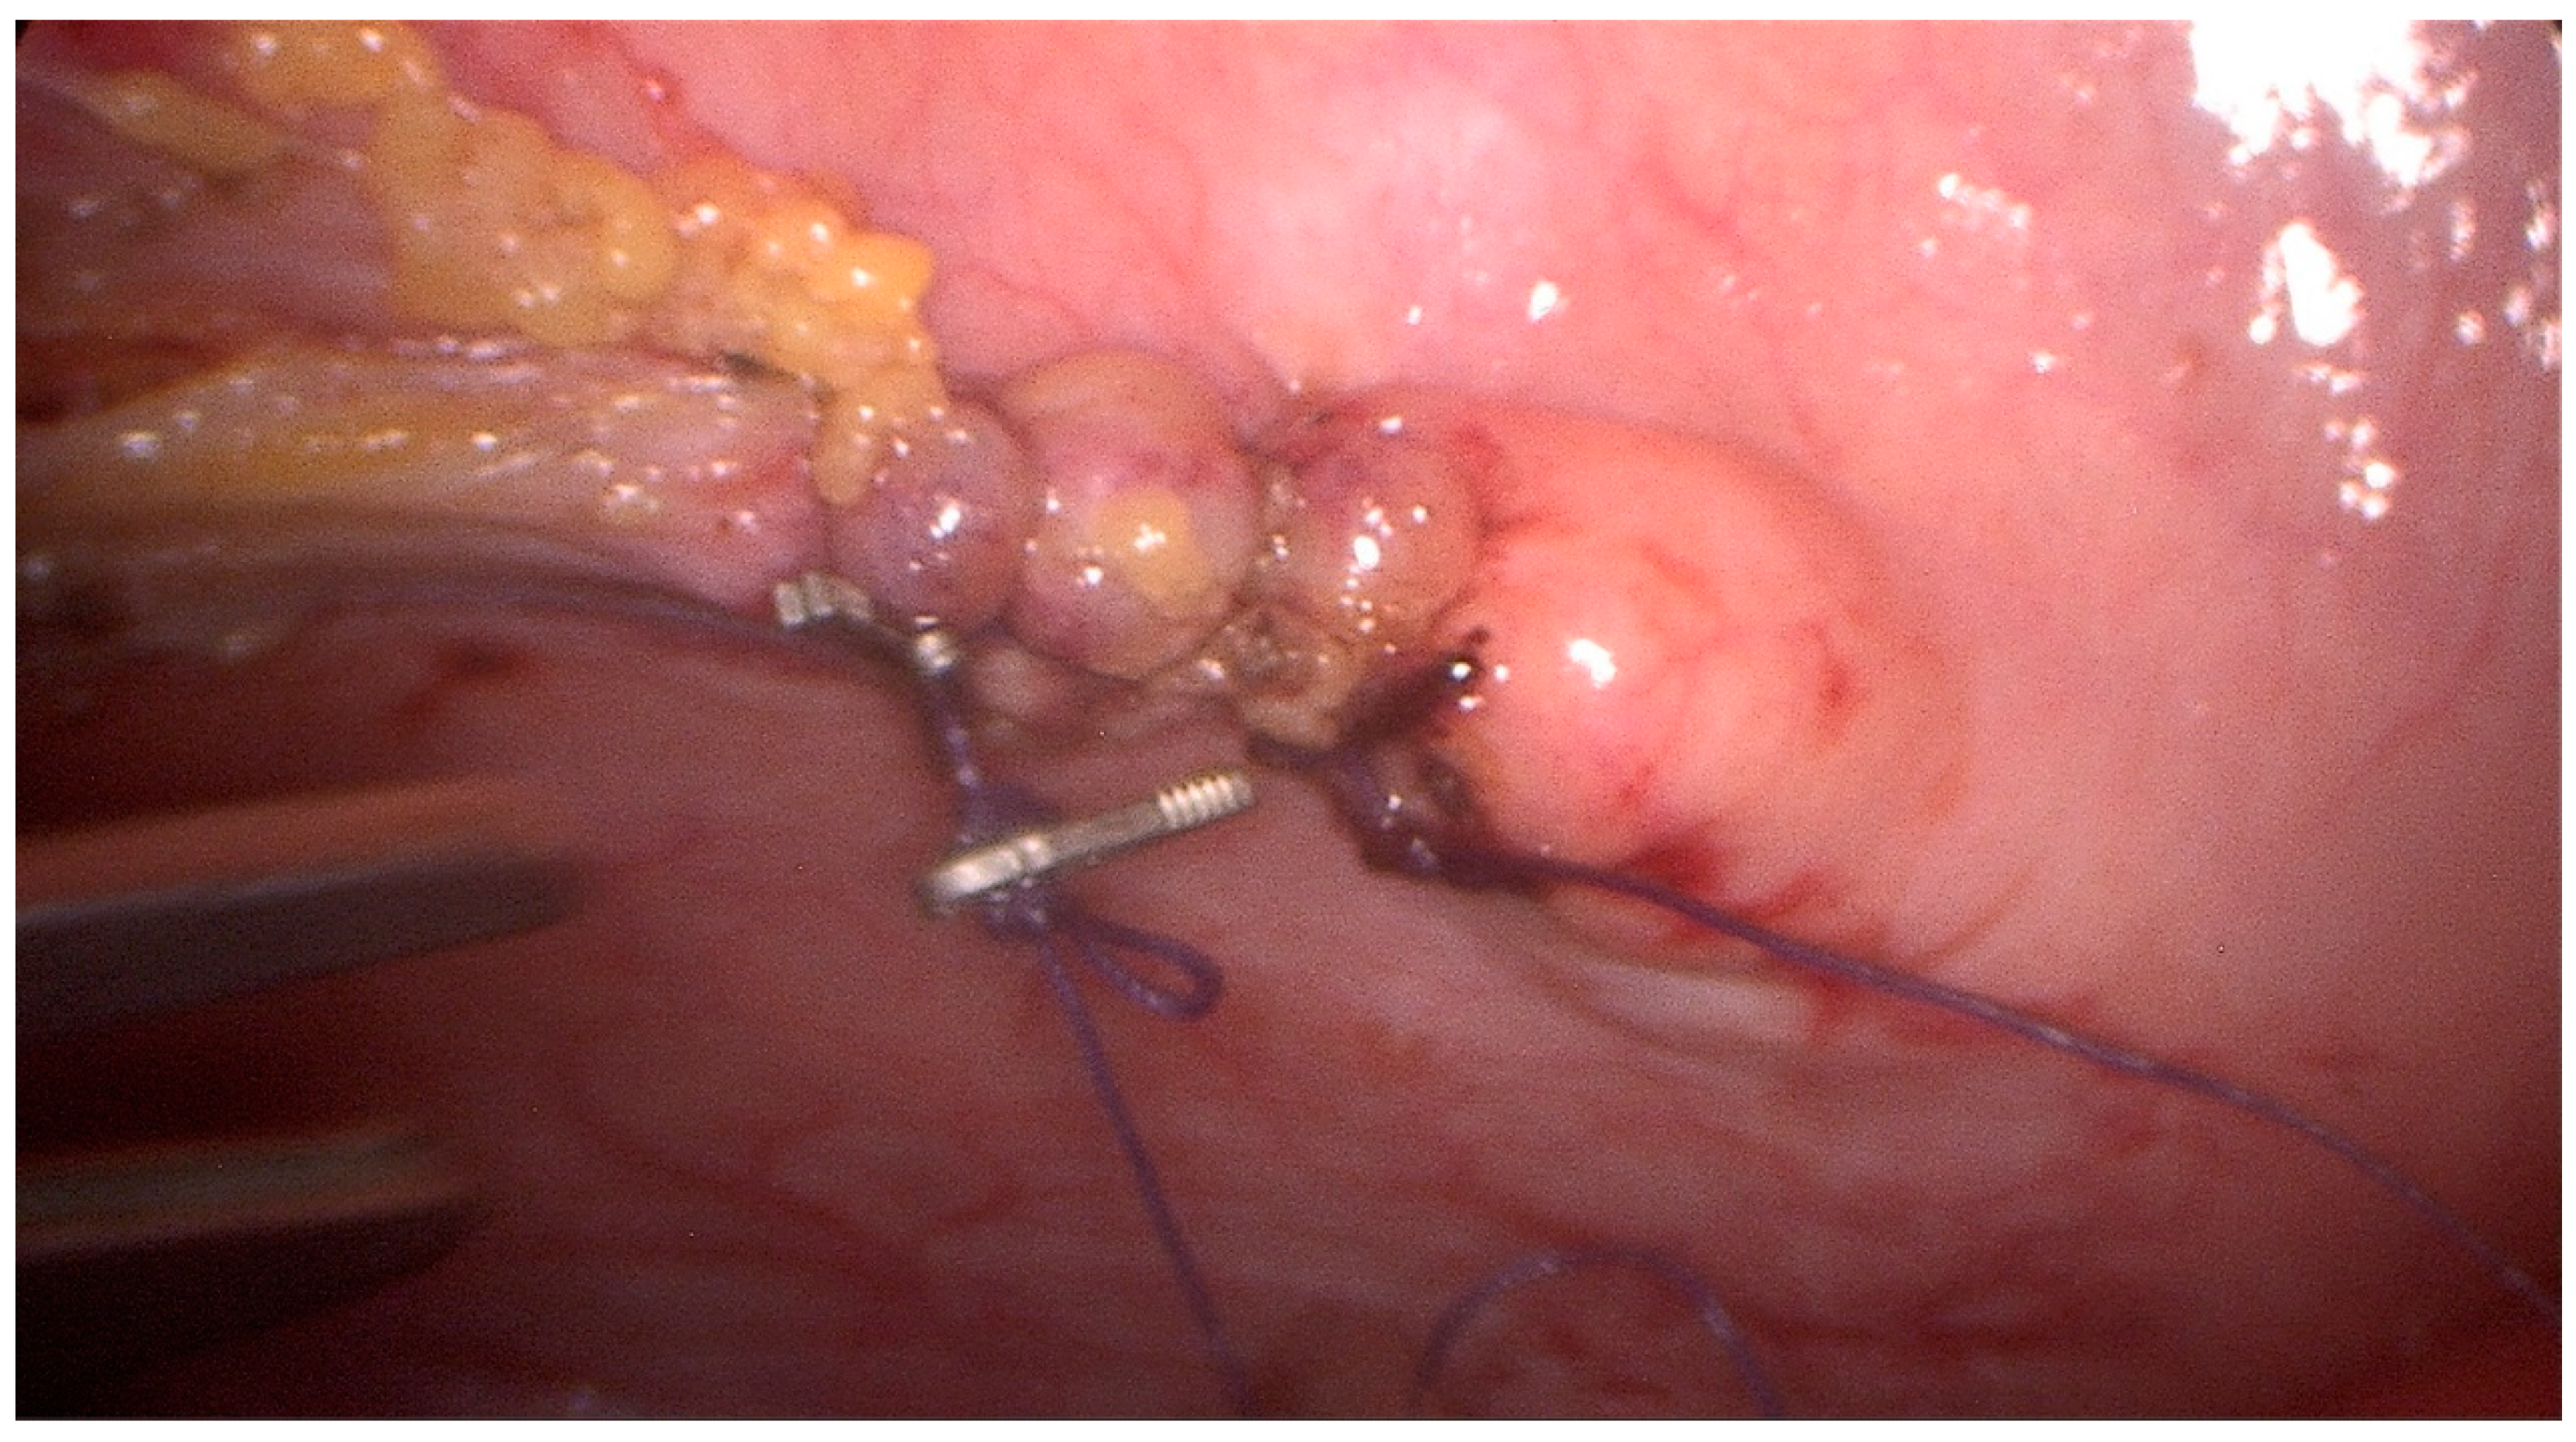

2. Case Description